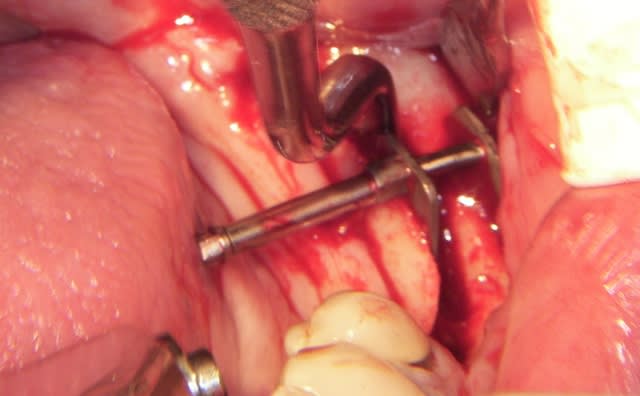

L’incision est décalée par rapport à la crête, en vestibulaire, car je ne veux pas décoller le périoste sur la partie osseuse qui est mobilisée.

Je pense que ça permet de "nourrir" le "greffon" et surtout si la table interne venait à se rompre le "greffon" ne serait que semi-mobile.

Quelques fois oui mais dans ce cas je voulais gagner 5/7 mm en hauteur pas en largeur et j’avais choisi avant de ne faire que la chirurgie (d’autant plus que c’est un cas que je dois présenter et finir en posant 3 ou 4 implants à droite et à gauche) en démo chez Anthogyr.

Coté droit il y a la hauteur mais pas de largeur, coté gauche manque de hauteur (je n’aime pas les implants de moins de 10 mm)

J’ai donc fait une expansion verticale et latérale puisque je n’ai pas coupé la corticale linguale, du moins dans sa partie postérieure, et j’espère gagner sur les deux tableaux, mais il était risqué de mettre en plus les implants.

quelques photos en "grand"

Il y a deux incisions séparées de 1,5 à 2mm, initiées au disque (double comme sur les motos) et finies au piézo

Il est illusoire de croire que l'os mandibulaire se laisse "pénétrer" simplement.

Et surtout il faut pouvoir retirer le distracteur ensuite.